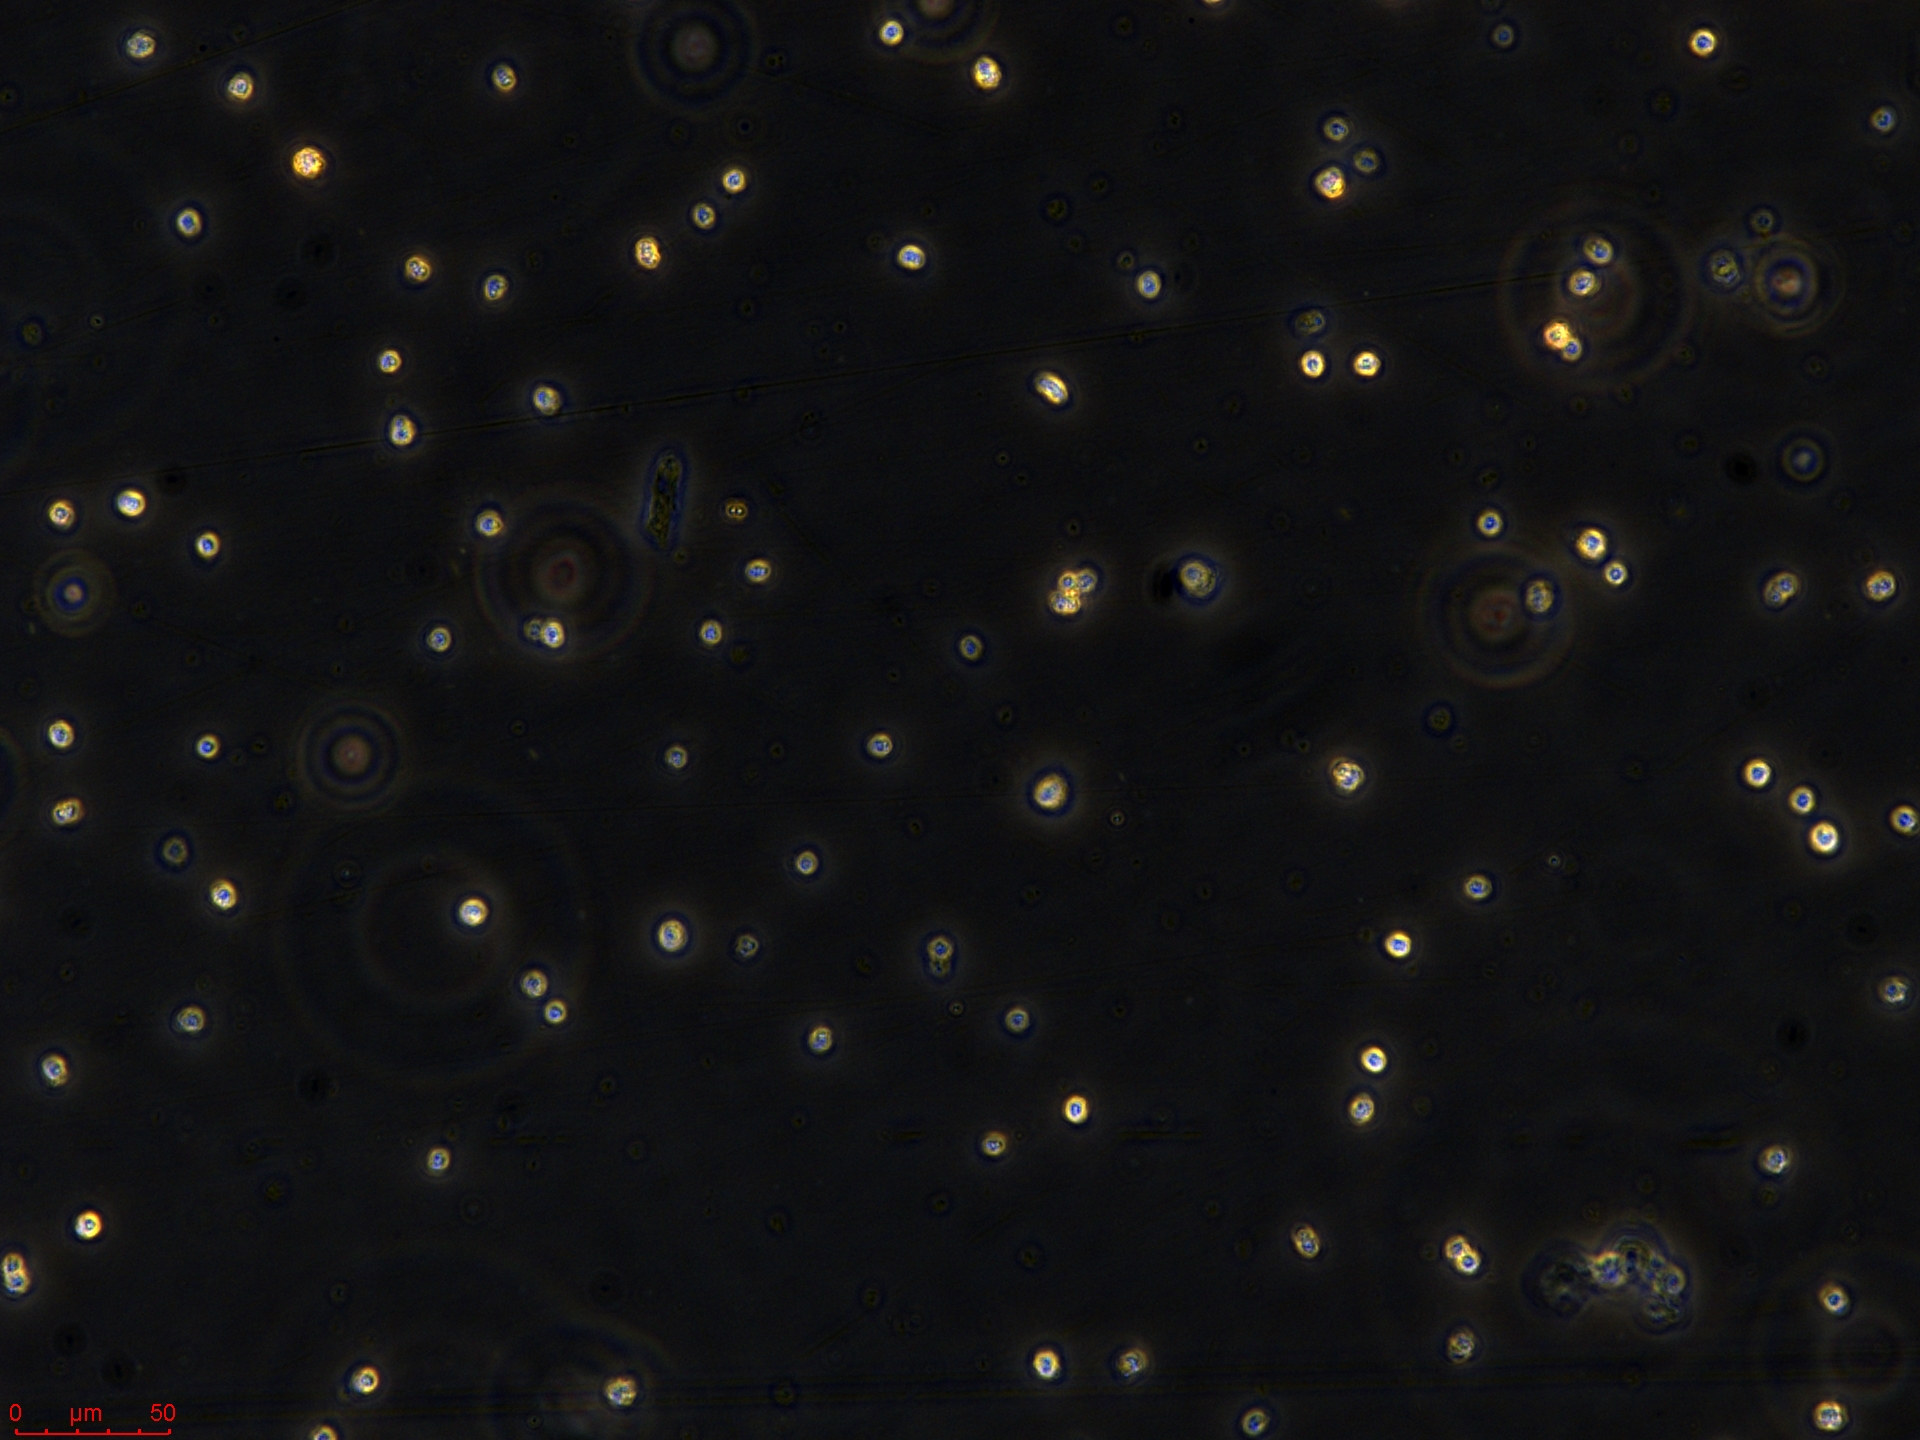

悬浮生长(Suspension)

分析核型,而且能分选出不同类型的染色体,做成人类每条染色体的 DNA 文库,可用于人类基因组研究、遗传病和癌症的诊断的研究。 免疫学研究 结合免疫荧光方法,流式细胞术可辨认和计数带有不同表面特异性抗原的细胞,例如用荧光素标记的免疫球蛋白鉴别T和B淋巴细胞,根据细胞表面抗原的不同,进一步分辨出不同的 T 和 B 淋巴细胞亚群,以及测定每个细胞所带抗原的数量、密度及其动力学参数等。也可用流式细胞分选技术将带有「+」和不带有「-」的某种特异抗原的细胞群体分类收集,供研究其功能特性。 流式细胞